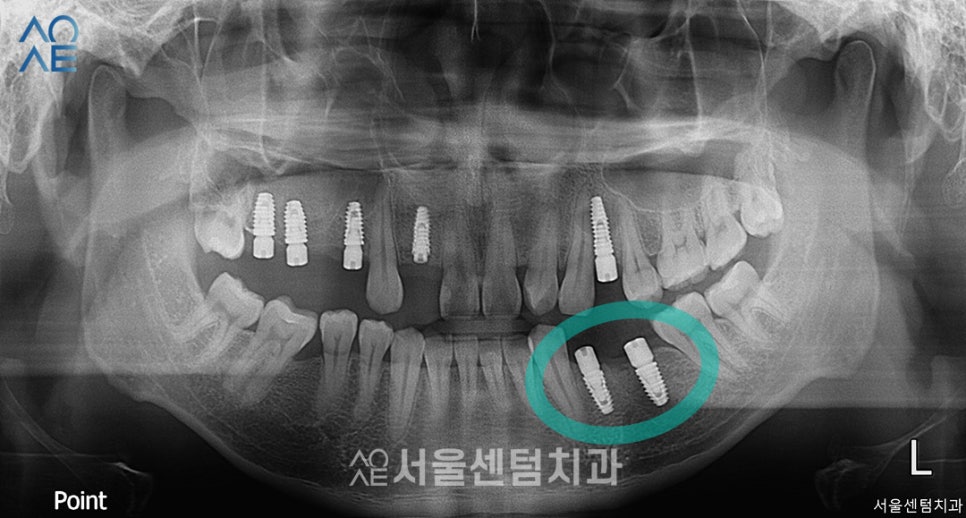

앞니 2차 수술과 보철물까지 장착한 후 입니다.

이 환자분은 위에 치아가 없다보니

아랫니가 올라온 상태여서

보철물을 수복할 공간이 부족한 편이었습니다.

따라서 공간을 만들어주는 교합조정술도 진행하고

보철물을 장착했습니다.

보철물 영구 접착 후 3개월 검진에서

촬영한 사진과 비교입니다.

기간 알기 쉽게 사진마다

촬영한 날짜를 표시해두었습니다.

다행히 불편한 점 없다고 하셔서

6개월 검진 때 뵙기로 했습니다.

보통 이때는 일상생활에서의 불편함

예를들어 음식물이 자꾸 끼는지

교합에 불편함 없는지 등을 체크합니다.

임플란트 총 7개와 사랑니발치 등

정말 많은 치료를 진행하였는데요.

다행히 진료일정에 잘 맞춰주어서

기간 딜레이 없이 잘 마무리 되었습니다.